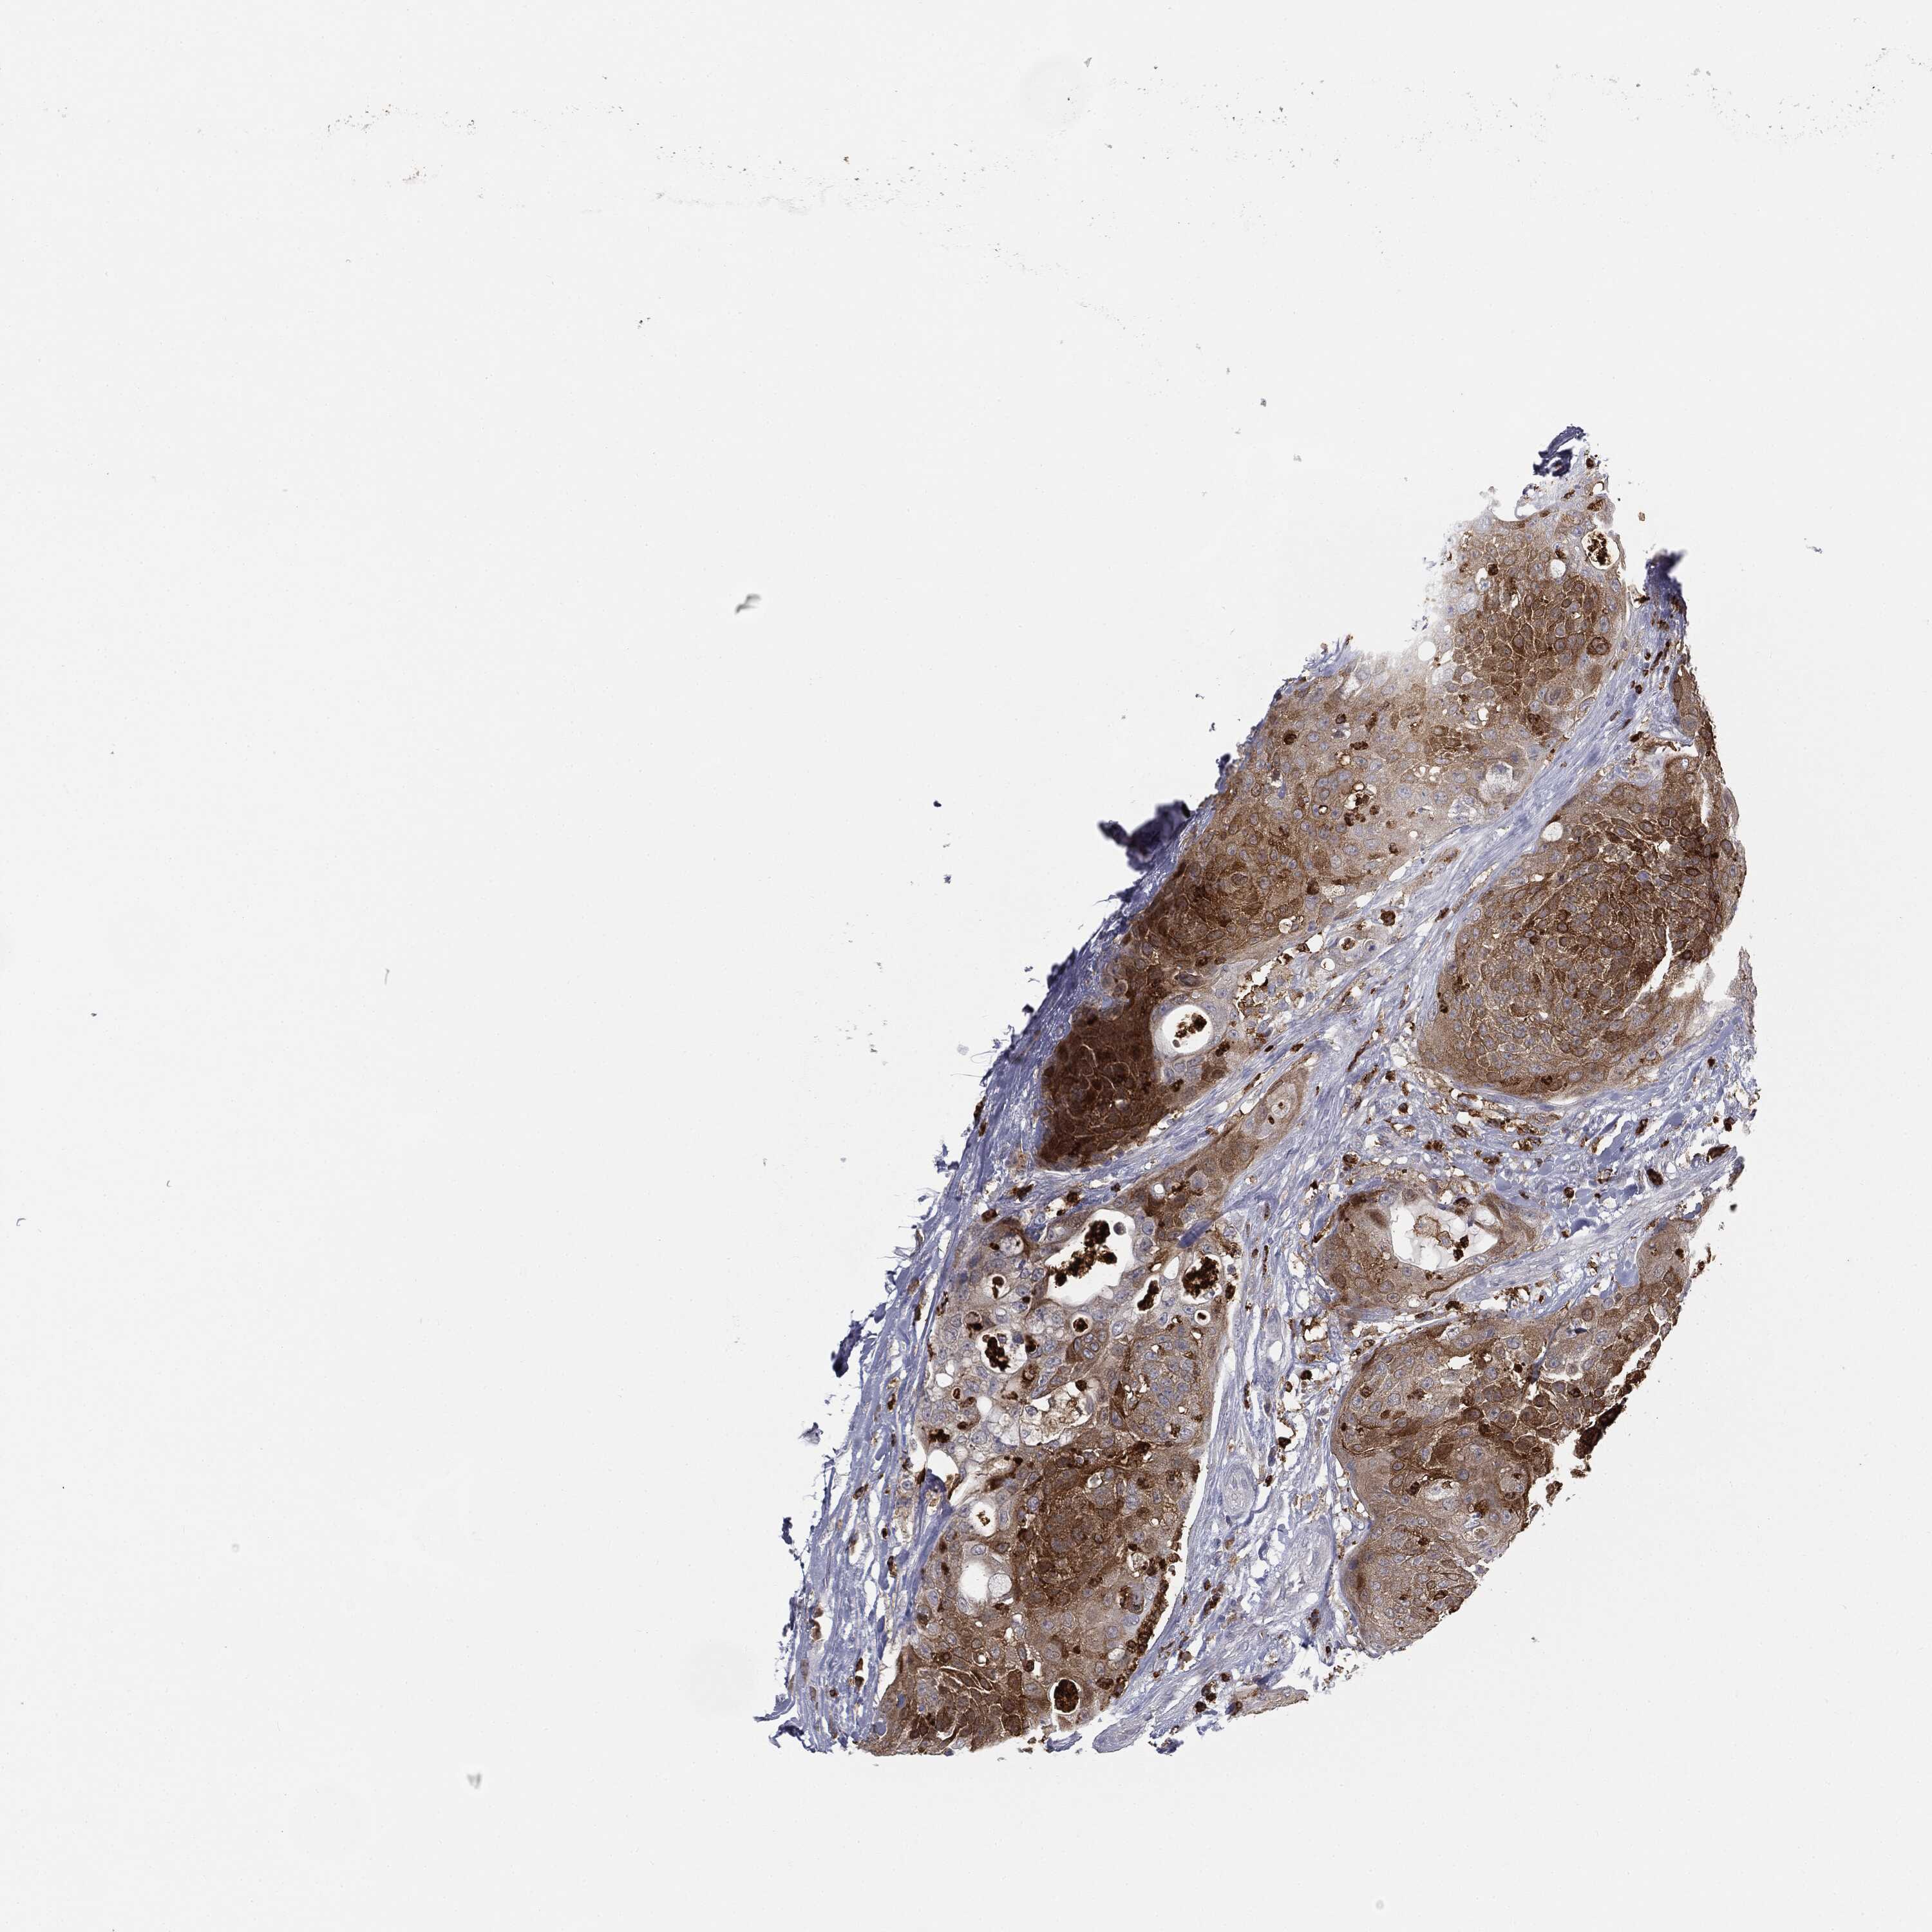

UROTHELIAL CANCER - Protein expressioni

A mouse-over function shows sample information and annotation data. Click on an image to view it in a full screen mode. Samples can be filtered based on level of antibody staining by selecting one or several of the following categories: high, medium, low and not detected. The assay and annotation is described here.

Antibody stainingi

Antibody staining in the annotated cell types in the current human tissue is reported as not detected, low, medium, or high, based on conventional immunohistochemistry profiling in selected tissues. This score is based on the combination of the staining intensity and fraction of stained cells.

Each image is clickable and will lead to virtual microscopy that enables deeper exploration of all samples and also displays staining intensity scores, fraction scores and subcellular localization as well as patient and tissue information for each sample.

Antibody HPA072667

Antibody CAB009492

Staining

High

Medium

Low

Not detected

Intensity

Strong

Moderate

Weak

Negative

Quantity

>75%

75%-25%

<25%

None

Location

Nuclear

Cytoplasmic/membranous

Cytoplasmic/membranous,nuclear

Urothelial carcinoma, High grade

Urothelial carcinoma, Low grade

Urothelial carcinoma, NOS